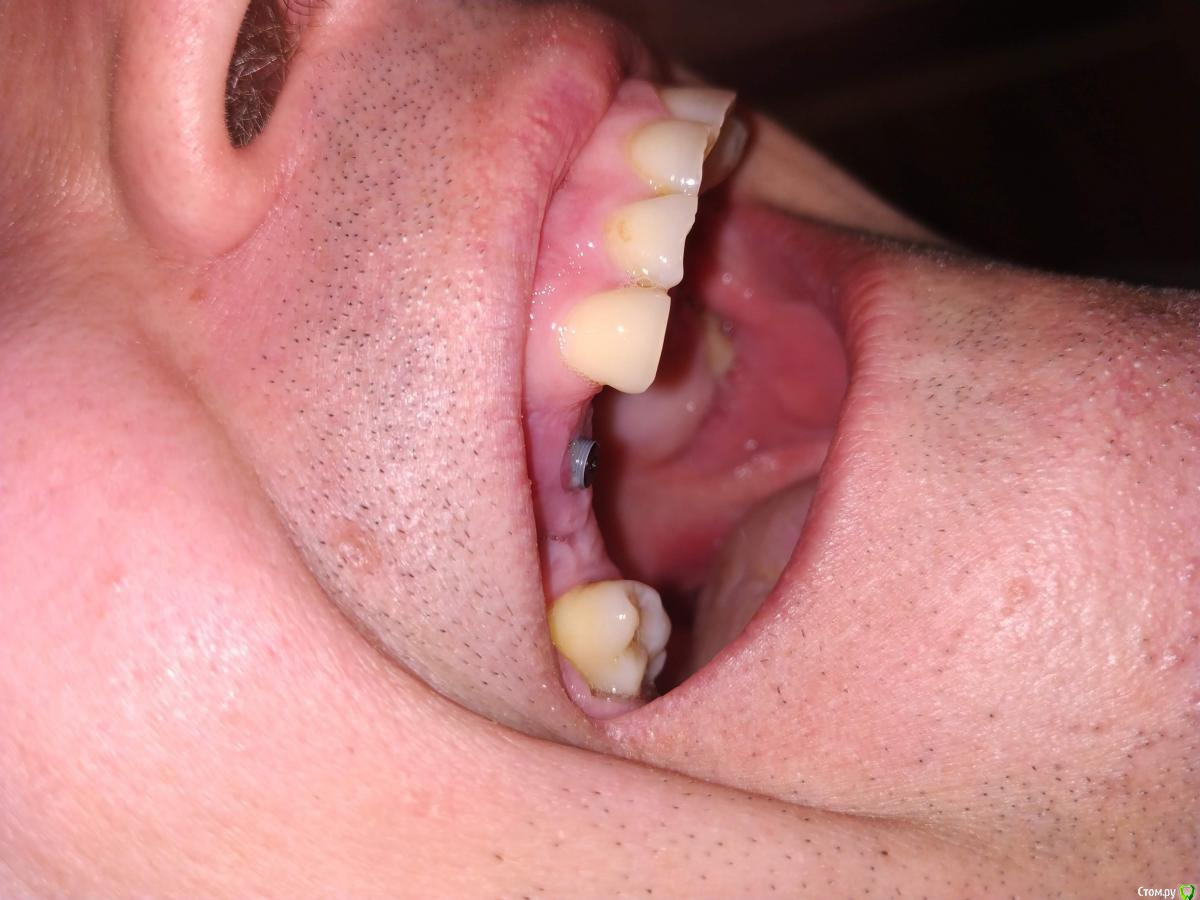

Валдемар Опубликовано 29 августа, 2019 Поделиться Опубликовано 29 августа, 2019 Добрый день,Уже был здесь, но прошлые явки и пароли забыл.12.04 операция 4 импланта20.04 вылез первый15.05 вылез второй26.08 удален 3ий28.08 удален 4ыйПотрачено 100тр, время и нервы. Возвращено 7200 за 2 импланта, за 2 которые удаляли деньги не вернули, так как не было показаний. А то что голова болит, переносица, лоб - ет не от этого. Удалил и всё прошло, кстати.Вопрос:1). Справа десны (кости) реально меньше чет слева. Что с этим делать. Как сделать чтобы кости хоть немного прибавилось? Без имплантации, просто кость с десной нарастить.2) 100% неприживаемости - ето как? Диабет, спид, гепатит по диспансаризации сдавал - отрицательно. Какие мои действия теперь? по новой имплантироваться и если опять не приживется, опять по новой? Ссылка на комментарий

Валдемар Опубликовано 31 августа, 2019 Автор Поделиться Опубликовано 31 августа, 2019 Я снимок после удаления не делал, но у меня реально справа десна тоньще раза в два. Там воспаление месяца два шло. В имплантацию больше не верю, вернее, боюсь. Боюсь нового стресса для организма. Верил в современную медицину, российскую, смотрел на людей с коленками кривыми, тазобедренными суставами проблемными, говорил че вы ждете, щас раз и коленку и тазобед сустав меняют и как новенький, а теперь понимаю, фиг там. Китайское что рибудь поставят, или руки у дохтора не оттудава, и всё, можно на костылях оставшуюся жизнь бегать...Потому люди до последнего и тянут. Ссылка на комментарий